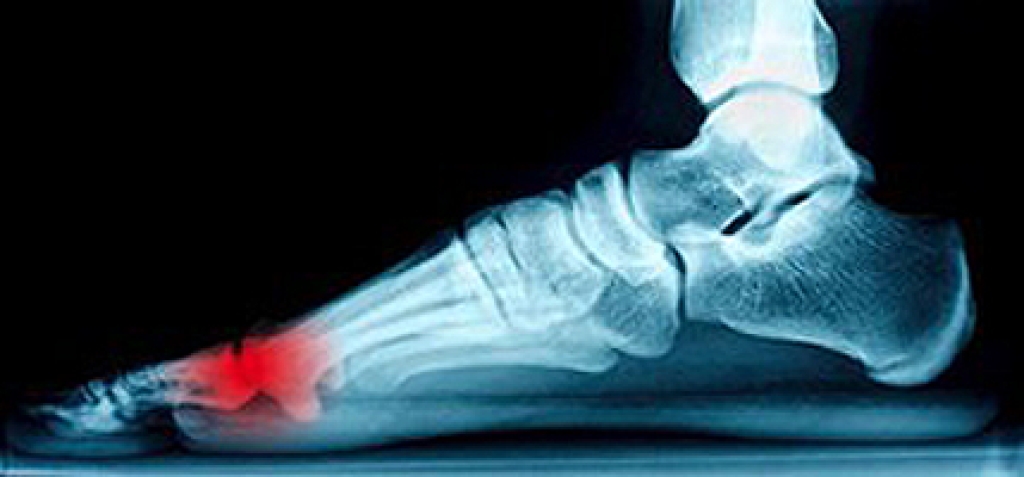

There are several different types of ankle injuries that many people endure. One of the most common is a sprain, and this may be a result of numerous causes. Despite the fact that many people who are actively involved in sports may suffer from this ailment, people from all walks of life may suffer from ankle sprains. Additionally, a fracture in the ankle bones may produce significant discomfort and pain, and can be properly diagnosed by having an X-ray performed. A medical condition that is referred to as ankle tendinopathies is a result of torn or ruptured tendons that encase the ankle, which typically provides stability to the foot. When these tendons become torn and inflamed, the foot may have endured overuse or may have possibly been involved in a trauma. Arthritis in the ankle can be extremely painful and this may be the result of degenerative bone conditions. Please consult with a podiatrist if you have endured an ankle injury so the best course of treatment can begin.

Due to the wide variety of potential causes of ankle pain, podiatrists will utilize a number of different methods to properly diagnose ankle pain. This can include asking for personal and family medical histories and of any recent injuries. Further diagnosis may include sensation tests, a physical examination, and potentially x-rays or other imaging tests.